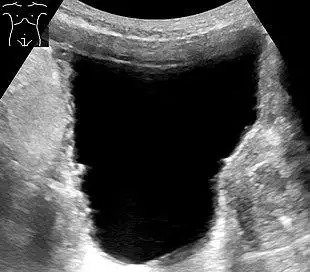

Ultrasound of the urinary bladder

Ultrasound of the urinary bladder of an 85-year-old man. It shows a trabeculated wall, which is a sign of urinary retention.

• Ultrasound – sound waves are used to visualize the kidneys and urinary bladder, assess the capacity of the bladder before voiding, and the remaining amount of urine after voiding. This helps know if there's a problem in emptying.